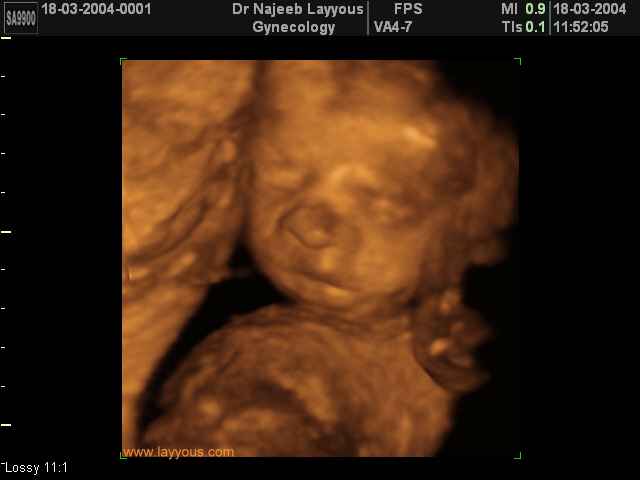

صور لوجه الجنين بجهاز الالتراساوند ثلاثي الأبعاد | الدكتور نجيب ليوس

صور لوجه الجنين بجهاز الموجات فوق صوتية ثلاثي الأبعاد